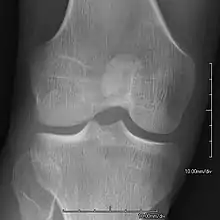

- Patellar involvement is present in approximately 90% of patients; however, patellar aplasia occurs in only 20%.

- In instances in which the patellae are smaller or luxated, the knees may be unstable.

An elbow of a man with nail–patella syndrome (NPS)

This is a view from a different angle of the same man's other elbow